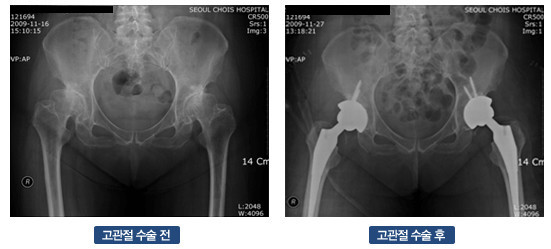

- 인공관절 치환술: 가장 일반적인 고관절 수술입니다. 퇴행성 관절염이나 심한 외상으로 인해 고관절이 손상된 경우, 인공 관절로 대체합니다. 이 수술은 대개 1-2시간 가량 소요되며, 회복이 길어질 수 있습니다.

- 진단적 검사: 의사가 필요할 경우 정기적으로 X-ray나 MRI를 통해 관절의 상태를 체크할 수 있습니다.